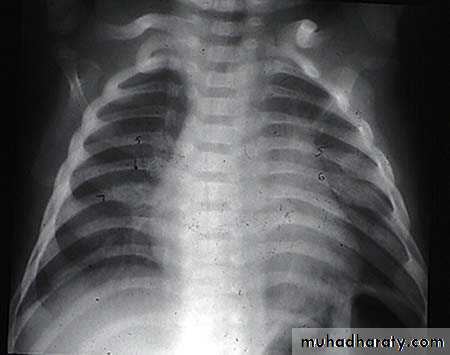

أشعة الصدر لطفل معذب، لاحظ الكسور المتسلسلة في الاضلاع

كسور الأجزاء الخلفية من الأضلاع